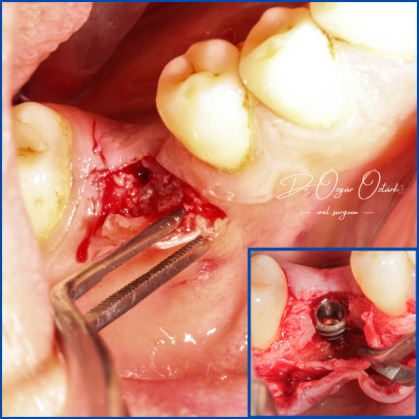

Kist nedeni ile çene kemiğinde defekt oluşmuş vakamıza sert ve yumuşak doku ogmentasyonu uyguladık